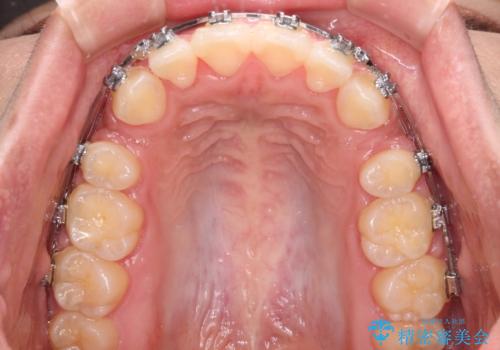

- メタルブラケット

- 3年1ヶ月

- 30回以上

上下の前歯が前方に突出していたため、上下左右の第一小臼歯4本を抜歯し、ワイヤー装置にて抜歯矯正を行うこととしました。

上下前歯部の被蓋関係を改善するの時間がかかり、3年間を要することとなりましたが、スッキリとした口元に仕上がりました。